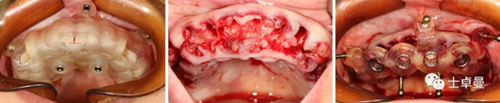

上頜種植手術

常規(guī)消毒碧藍麻局麻下,利用牙支持式導板確定固位釘位置后取下導板;

然后分離牙齦,于牙槽嵴頰腭側略翻瓣暴露牙根與牙槽骨間隙,切除齦瓣邊緣炎性肉芽組織,拔除上頜16-27牙,球鉆清理拔牙窩,并用大量生理鹽水沖洗;

通過先前固位釘位置安放固位釘支持式種植導板,因拔牙前后軟硬組織變化較大,需耐心尋找先前固位釘位置;

導板就位后利用Straumann BLT全程導板工具盒全程備洞,取下導板后利用測量桿確認種植體窩方向和深度以及種植窩周圍骨量;

植入6顆Straumann BLT種植體,植入扭矩均達到45Ncm以上:

16、26:4.1mm×14mm

14、24:4.1mm×12mm

12、22:3.3mm×12mm

安裝SRA基臺,均加力至35Ncm:

16、26:RC30°4mmA型

14,24:RC17°2.5mmA型

12,22:NC17°2.5mmA型

旋入SRA基臺保護帽,修整粘膜,縫合。

下頜種植手術

手術操作流程與上頜基本一致,最終植入4顆Straumann BLT種植體,植入扭矩均達到45Ncm以上:

35、45:4.1mm×14mm

32、42:3.3mm×12mm

35、45:RC30°4mmA型

32、42:NC直型2.5mm